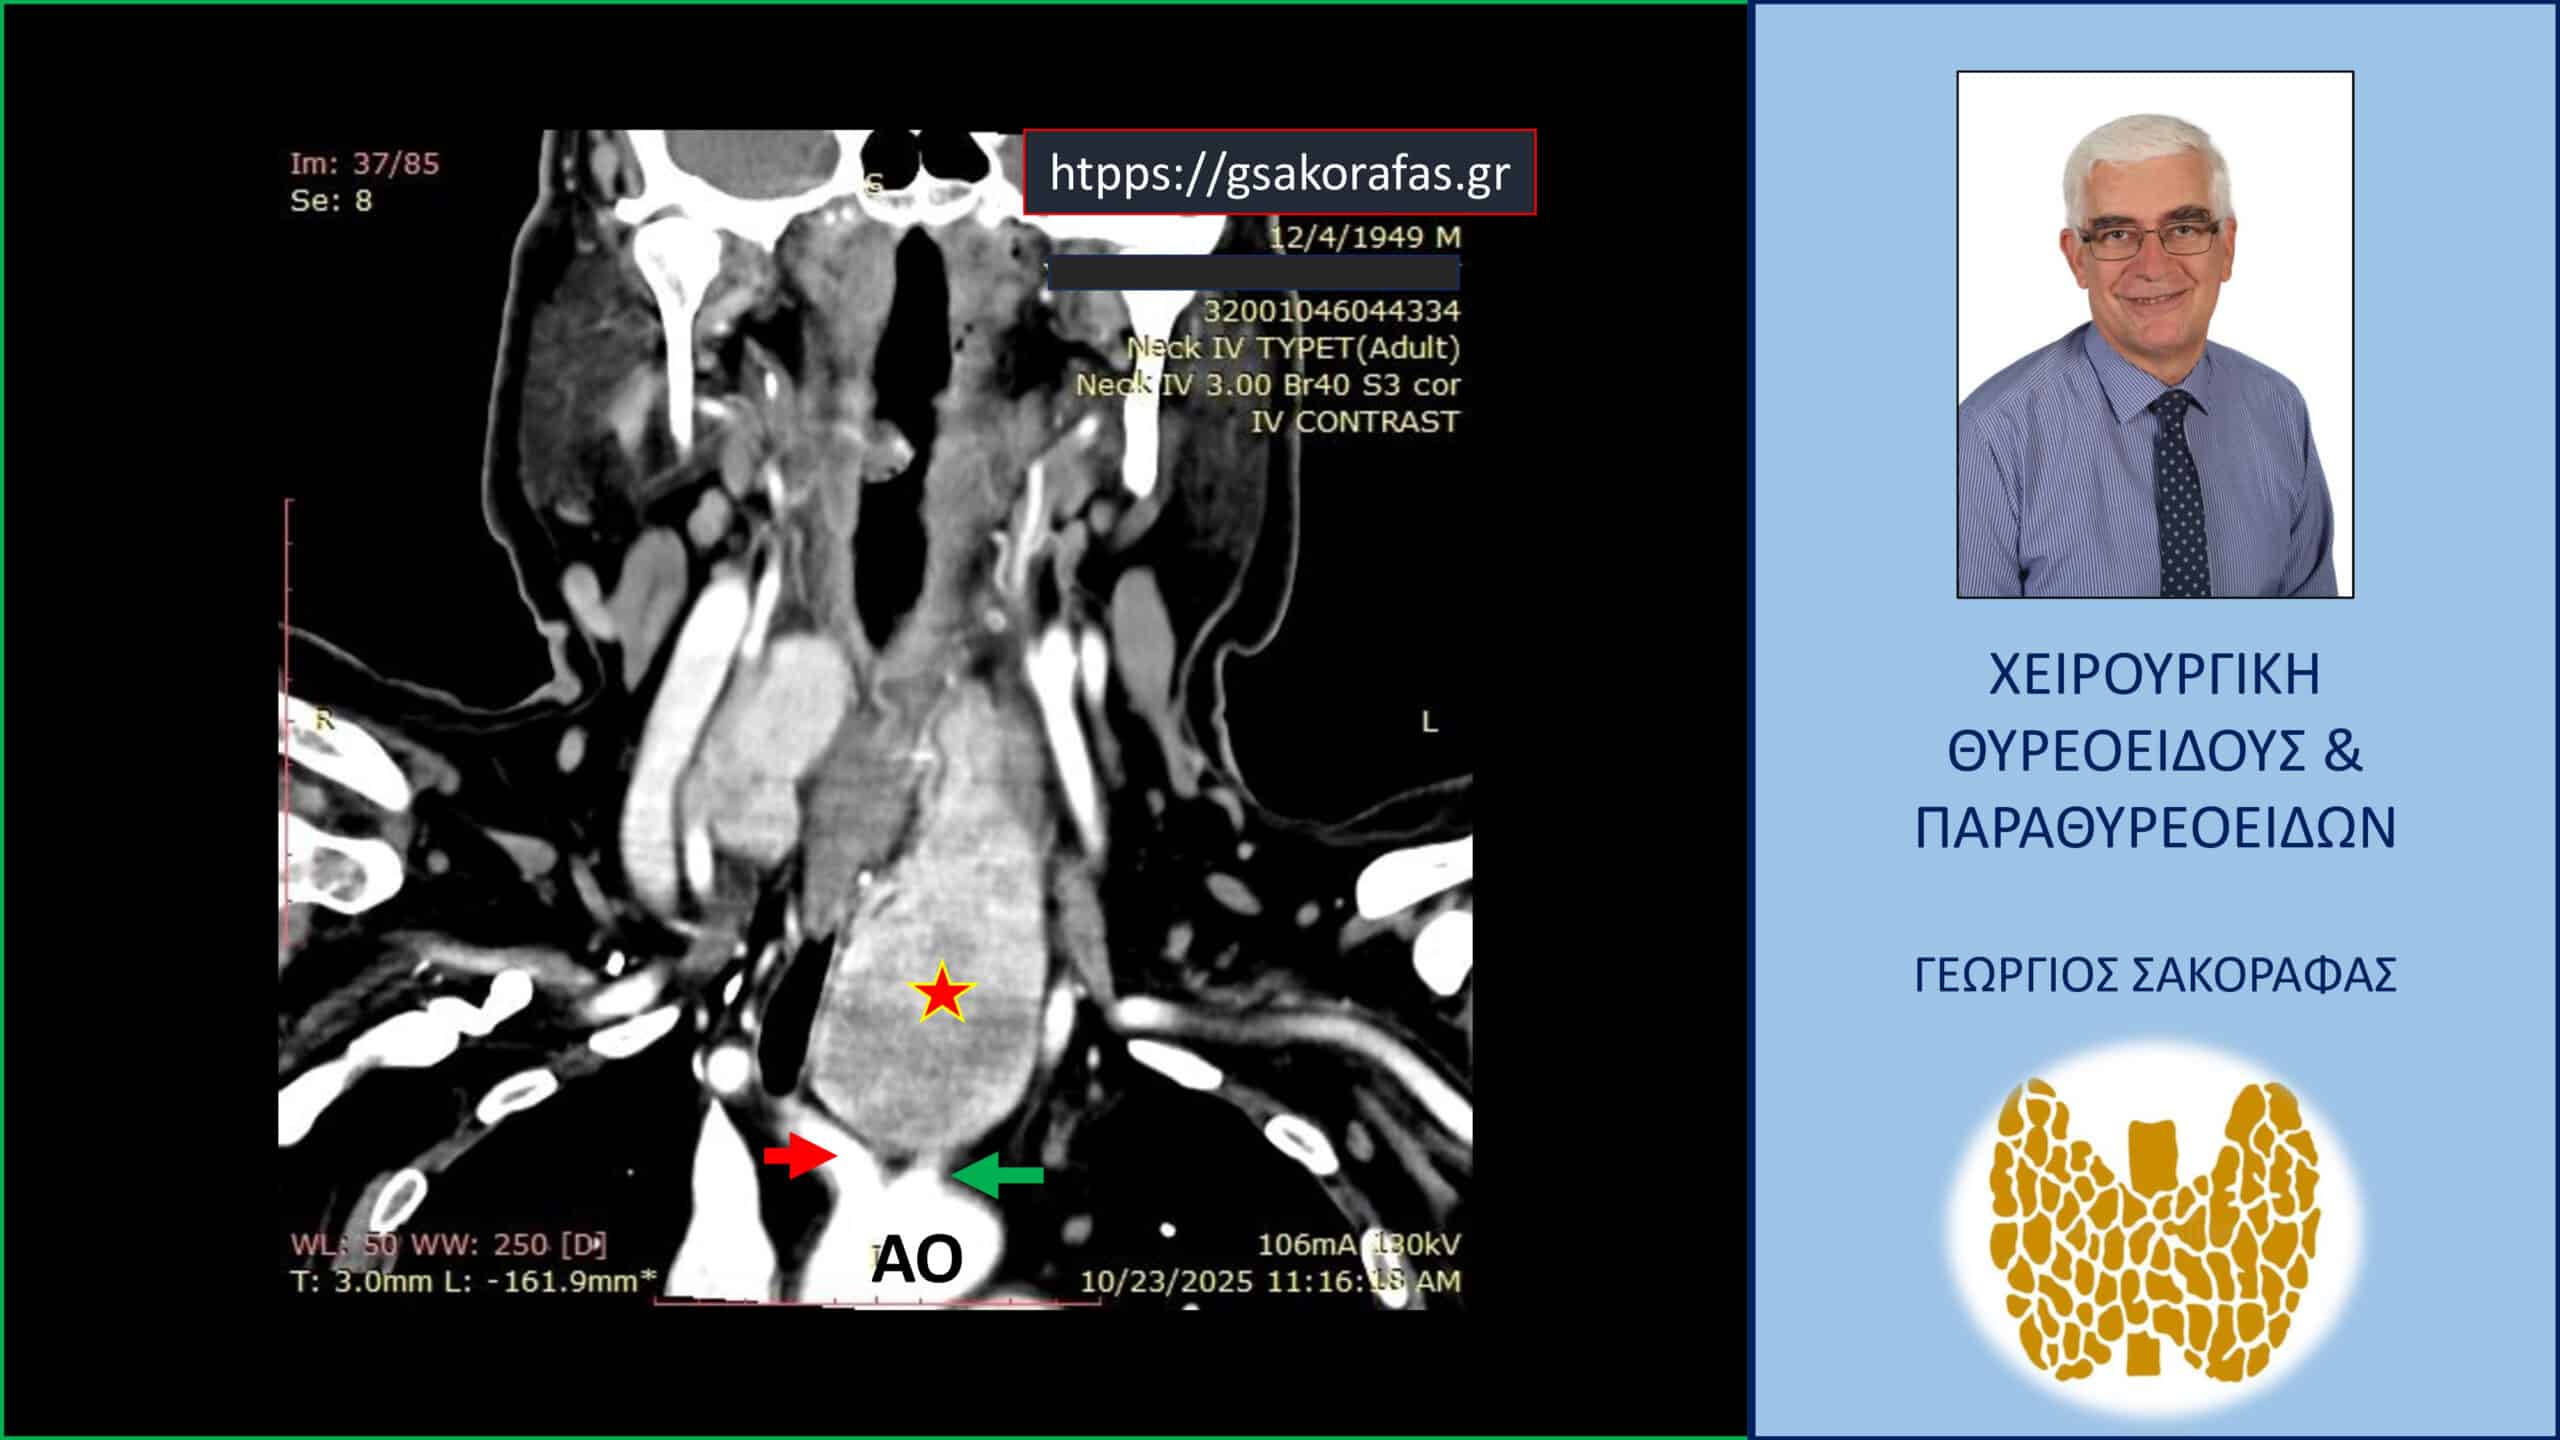

Γιγάντια καταδυόμενη βρογχοκήλη σε ασθενή με «δύσκολο» τράχηλο και βαθιά κατάδυση (μέχρι το αορτικό τόξο) – διατραχηλική εκτομή (χωρίς στερνοτομή) με ταυτόχρονη παραθυρεοειδεκτομή για τυχαία διαγνωσθέν αδένωμα παραθυρεοειδούς. Αξονική τομογραφία – εικόνα σε κατά μέτωπο διατομή: Ο καταδυόμενος αριστερός λοβός (κόκκινος αστερίσκος) εκτείνεται σε βάθος στο μεσοθωράκιο φθάνοντας στο άνω όριο του αορτικού τόξου (ΑΟ) μεταξύ της έκφυσης της ανωνύμου αρτηρίας (κόκκινο βέλος) και της αριστεράς κοινής καρωτίδας (πράσινο βέλος).